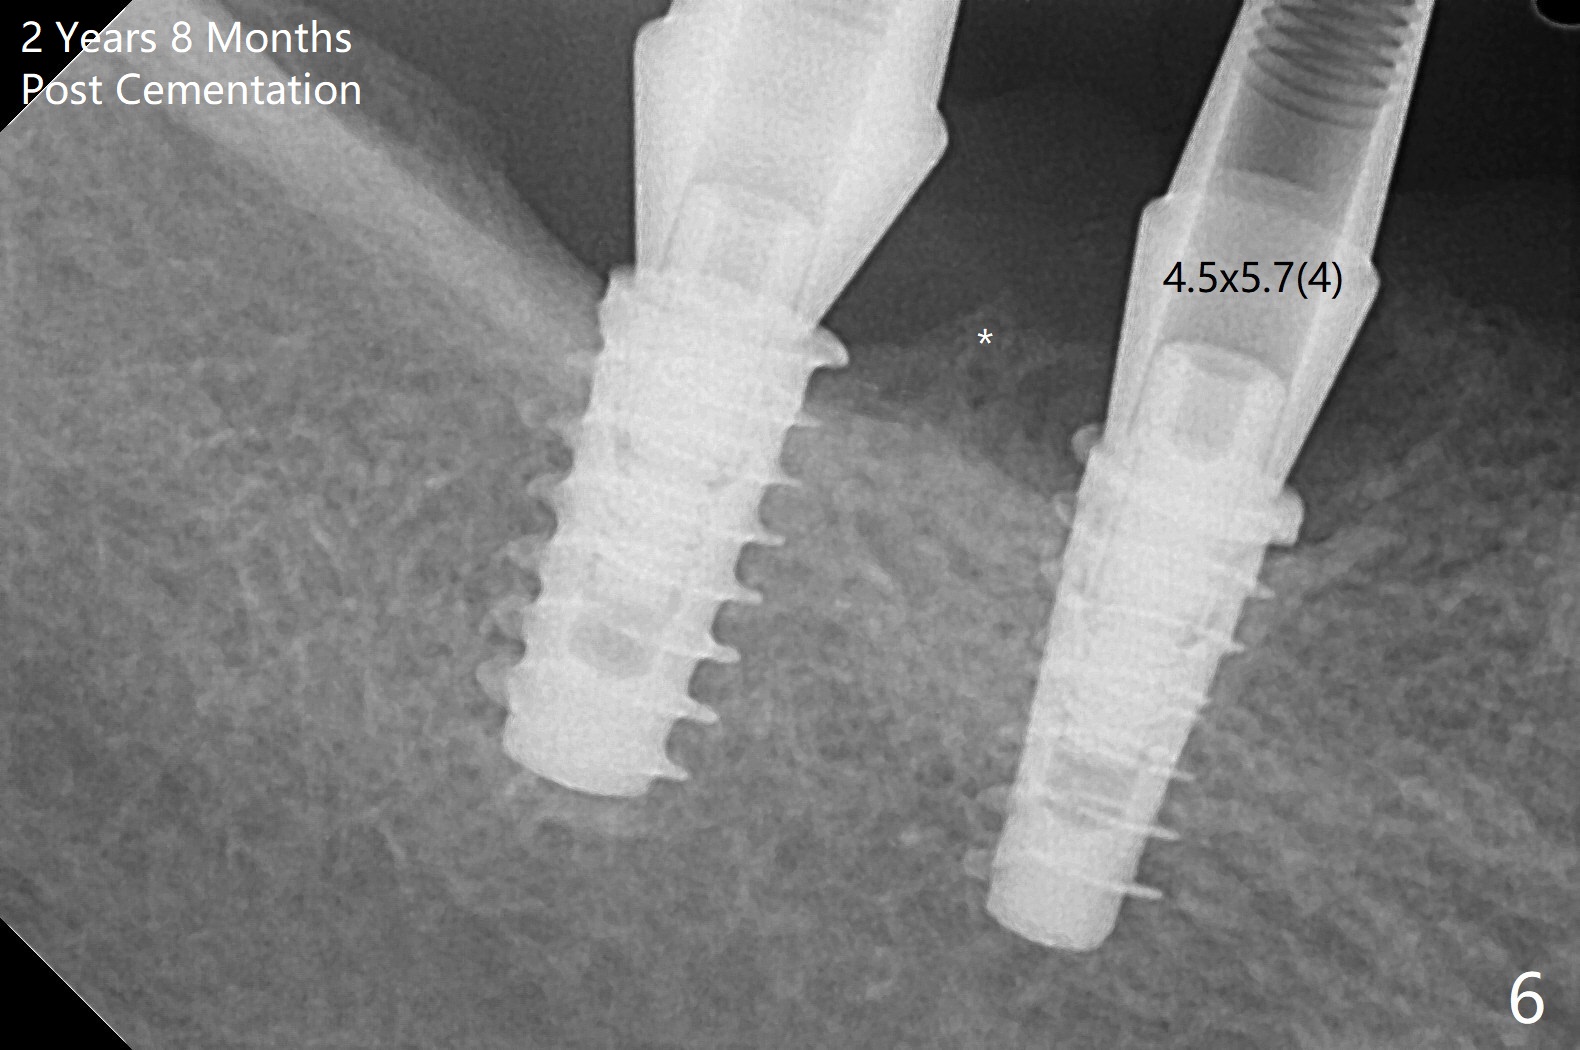

Following osteotomy, 4.5x11 and 5x9 mm dummy implants are placed at the sites of #30 and 31, respectively (Fig.1). Due to limited inventory of Magicore and patient's in-cooperation, FC implants (4.5x9 and 5x9 mm) are placed (Fig.2). A healing abutment (6x4 mm) is placed at #31 because of low torque (overprep), while a pair abutment (6.5x5.7(4) mm) is placed at #30. Vera Graft is placed with autogenous bone (*). The implant/abutment ratio at #30 is unfavorable. If the implant turns out to be loose, immediate implant should be larger in the future. Note bone growth, especially at #30, 2.5 and 4 months postop (Fig.3,4). In fact the abutments are incompletely seated. The crown of #30 is loose 2 years 8 months post cementation, while the abutment at #31 remains incompletely seated (Fig.5). The latter is completely reseated after separating the crown, while a smaller one is seated at #30 (Fig.6) due to use of a small healing abutment earlier (Fig.5). A good piece of news is the presence of the bone between the implants (Fig.5,6 *), which contributes to interimplant papilla. Return to Lower Molar Immediate Implant, Prevent Molar Periimplantitis (Protocols, Table), IBS77, 2-5 Xin Wei, DDS, PhD, MS 1st edition 09/22/2017, last revision 12/01/2020